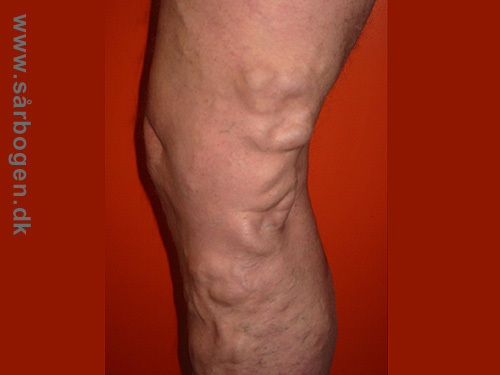

Magnavaricer

Zoom

Åreknuder